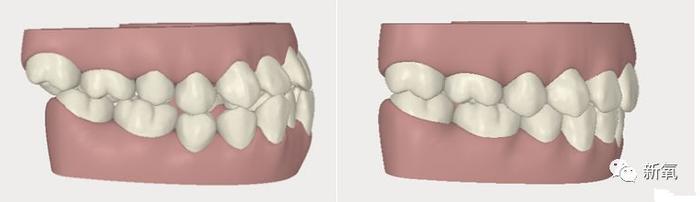

顺手科普,正常咬合和地包天(反颌)。

同样的道理,深覆盖、深覆合、龅牙嘴凸这些上颌过度发育的情况,也会明显影响下颌骨的发育。

所以我们常见的嘴凸、龅牙的例子,几乎都伴有下巴后缩、下颌短小等下颌骨发育不足的情况。

这种就是单纯的牙齿排列不齐,没啥骨骼问题的那种。 这一种情况也是今天三种情况里唯一年龄要求不高的。

换句话说,如果你只是牙列乱,即使现在已经年过半百,依然可以整牙(当然是有个小小前提的,下面总结的时候说)。不过,为了避免单纯牙列不齐造成不良习惯,官方建议:最佳矫正时间女孩是11-14岁,男孩是12-15岁。

所以成年人的矫正,大多是像潘粤明和高圆圆这样,单纯的将错乱的牙列整齐。对五官呐、骨骼甚至肌肉习惯都没啥影响了,颜值也就变化不大。